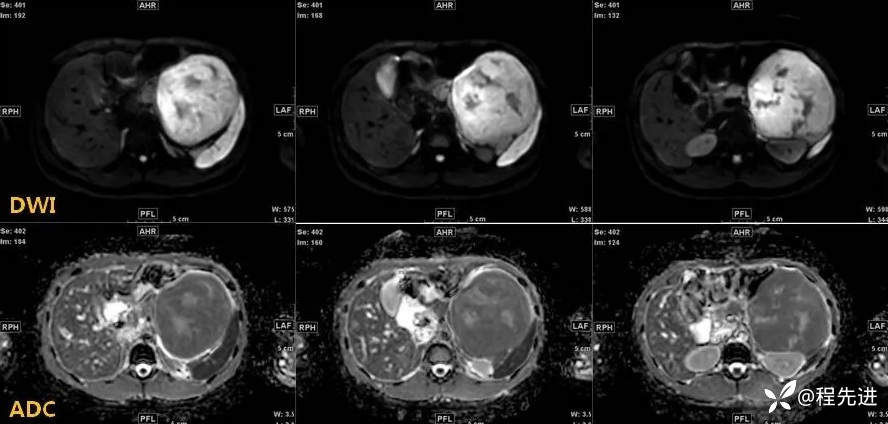

T1: